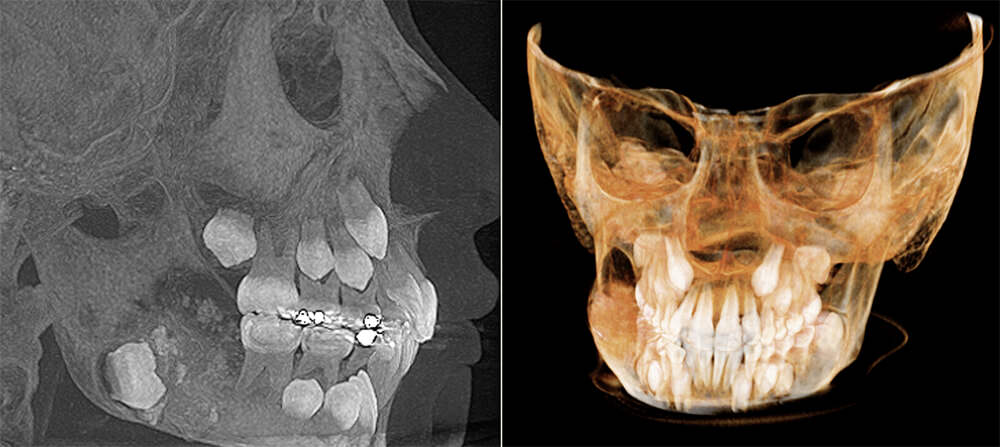

El estudio con Tomografía Computada Cone Beam, nos muestra una lesión de densidad mixta con predominio de hiperdensidad y limites corticados netos, que engloba al germen de la pieza dentaria 47, con expansión de las tablas óseas vestibular y lingual y el desplazamiento del conducto dentario inferior hacia el borde basilar del cuerpo mandibular, en tanto que a nivel de la rama ascendente se observa a este conducto desplazado hacia la cara interna de la misma. (Figura 2)

Figura 2: Estudio tomográfico donde se observa la lesión de FOA a nivel del gonion del lado derecho del maxilar inferior